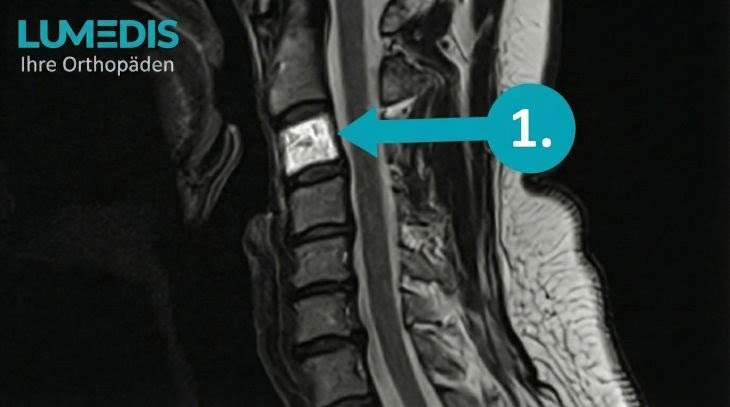

CT eines Hämangioms in der Brustwirbelsäule (TH10)

Wirbelkörperhämangiome sind häufig Zufallsbefunde, die im Rahmen einer Röntgen-, CT- oder MRT-Untersuchung entdeckt werden, die aufgrund einer anderen Erkrankung durchgeführt wurde. Sie erscheinen dabei im Röntegenbild als scharf begrenzte, vom restlichen Wirbelkörper abgehobene, dunkle Läsionen.

Treten chronische Schmerzen mit möglicherweise neurologischen Symptomen vor der Bildgebung auf, werden durch eine gründliche Anamnese sowie neurologische und orthopädische Untersuchungen alle möglichen Differentialdiagnosen ausgeschlossen. In der Regel erfolgt auch eine bildgebende Untersuchung wie CT, MRT oder Röntgen.

Aufgrund der typischen Darstellung von Hämangiomen in der Bildgebung können bösartige Tumoren oder Metastasen anhand ihrer Struktur gut ausgeschlossen werden. Bei unklarem Befund kann eine Biopsie zur sicheren Bestätigung des vermuteten Hämangioms durchgeführt werden.